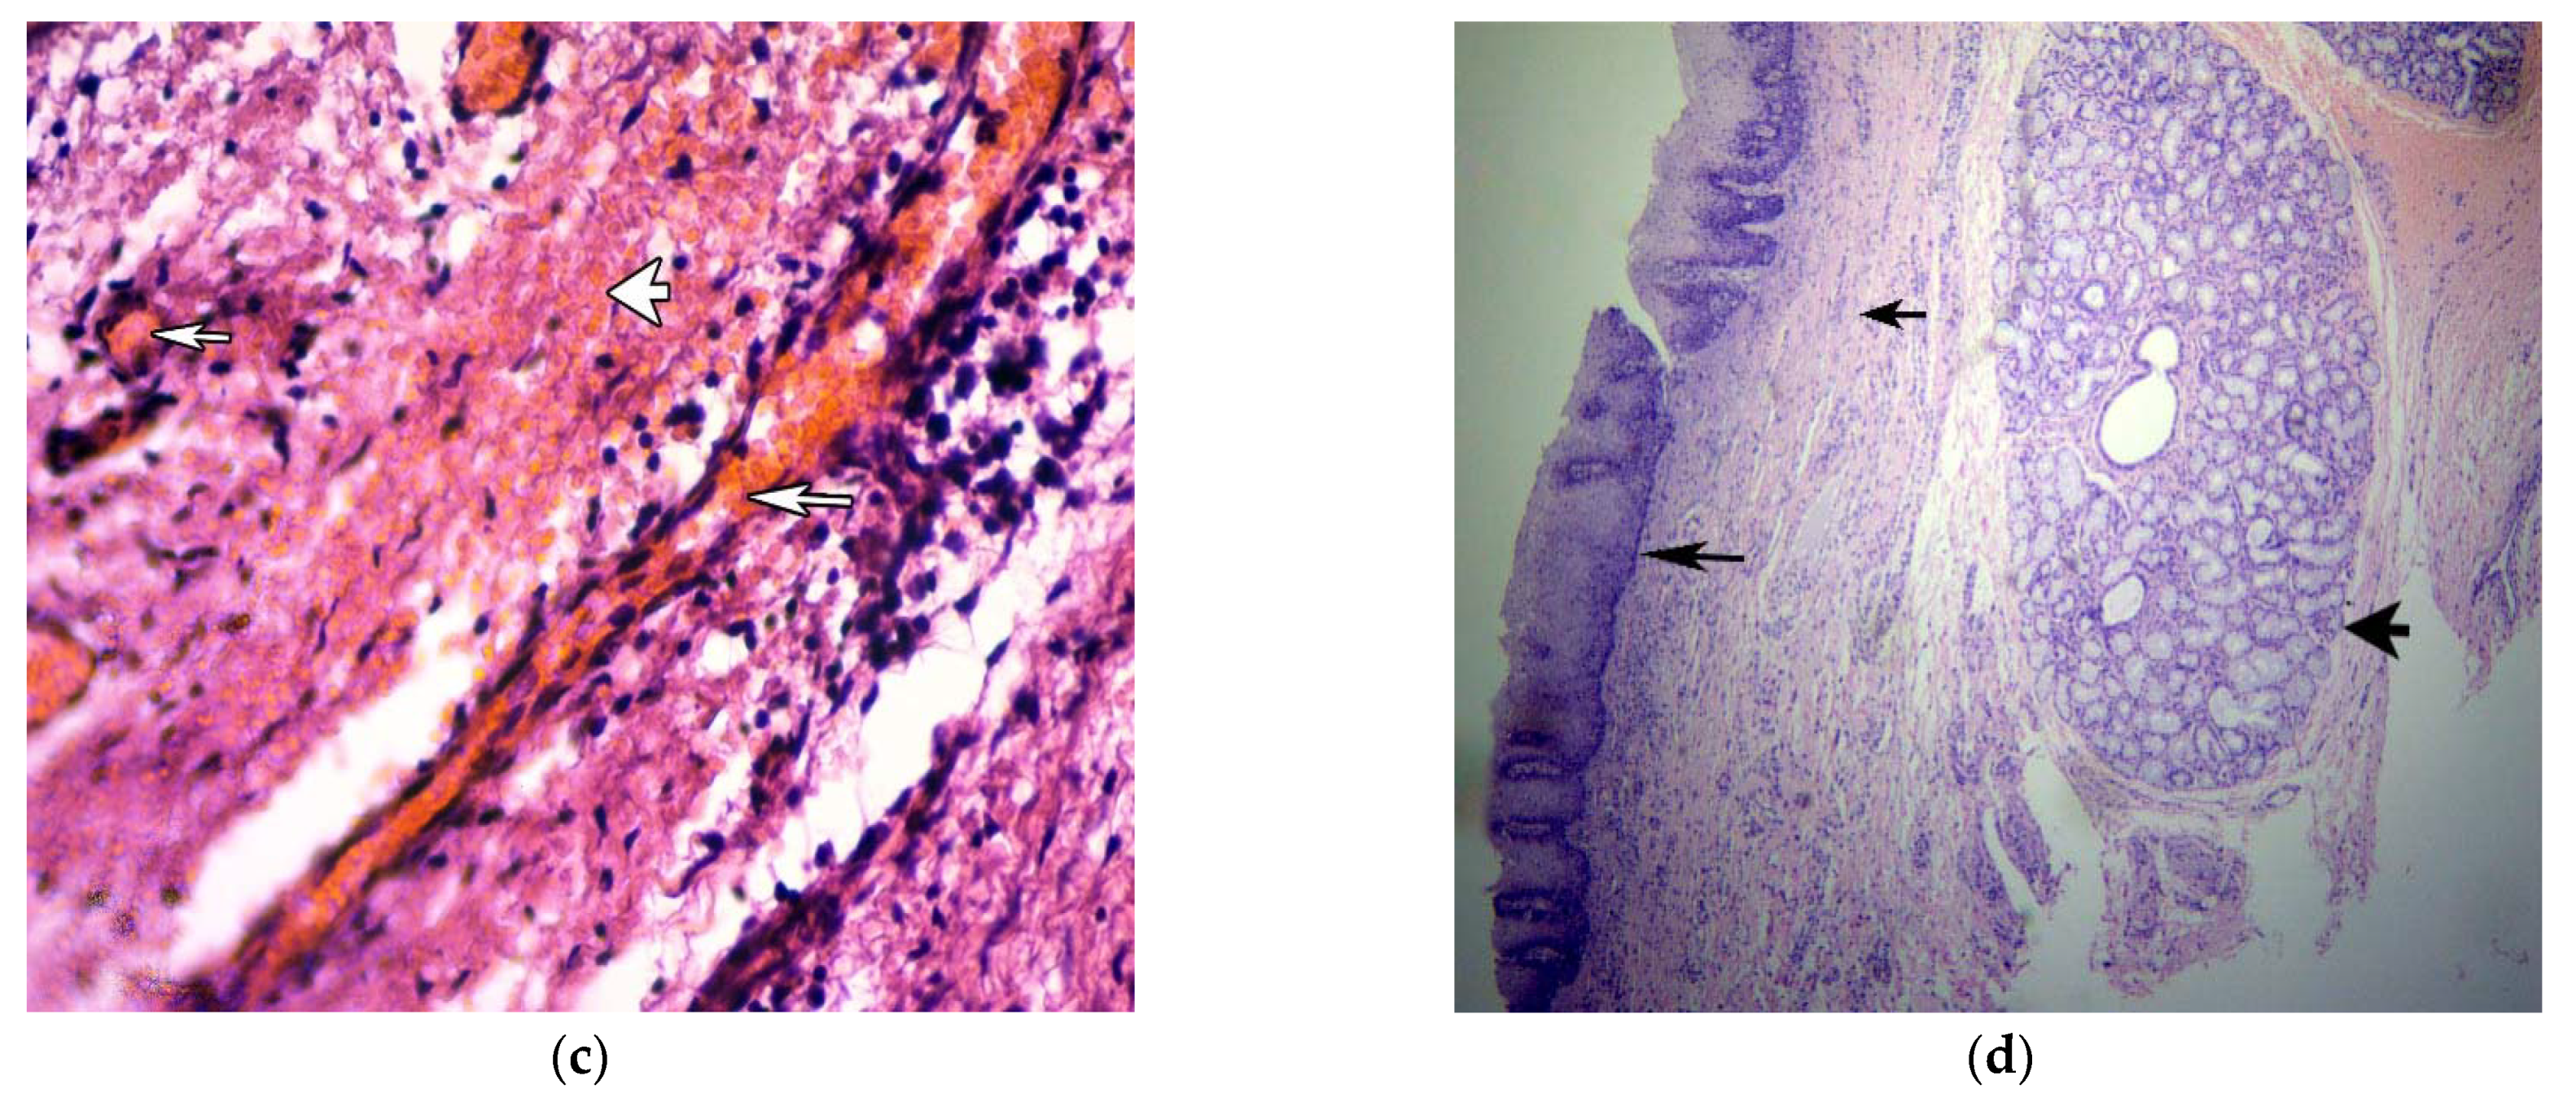

3.3. Pathohistological and Immunohistochemical Study